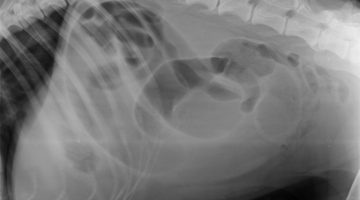

Veterinarska mafija u Hrvatskoj – mafija u hrvatskoj veterini. Veterinarska ambulanta Lonjica – Veterinarska stanica Vrbovec prikriva istinu o stručnoj pogrešci na mom psu. Napravili stručnu pogrešku, lžirali i krivotvorili nalaze, a u sve je upletena i Hrvatska veterinarska komora i predsjednik Visokog časnog suda Hrvatske veterinarske komore.